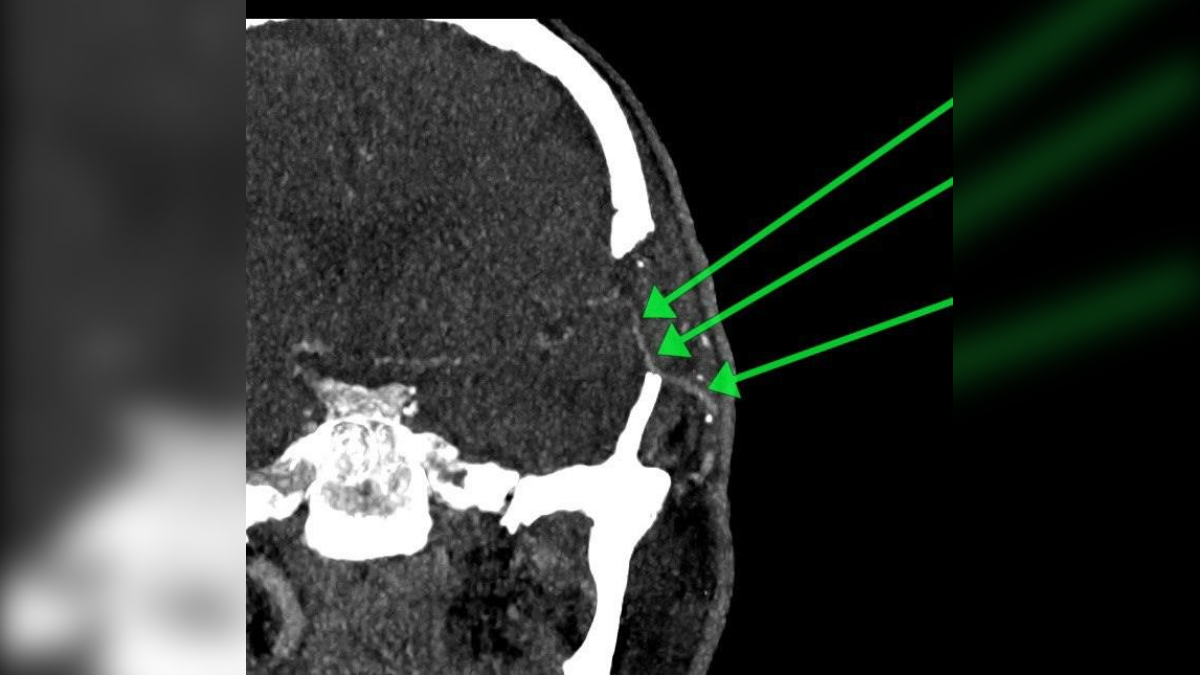

Хирурги подмосковной больницы спасли от риска повторного инсульта пациента. Они придумали способ, который позволил крови питать мозг в обход перекрытой первым инсультом артерии.

Врачи придумали «обходной путь» для кровотока, потому что после инсульта одна из артерий, питавших мозг, оказалась заблокирована. Из-за этого мозг пострадавшего начал работать с перебоями, возник высокий риск вторичного инсульта и огромных проблем для здоровья.

Тогда решили создать запасной проход для крови. Четыре часа хирурги сшивали сосуды, создавая новый путь кровотоку. Всё получилось: угрозу устранили, здоровье пациента спасли. Через месяц контрольное обследование показало, что созданный «обходной путь» работает без нареканий, сообщил портал 360.ru со ссылкой на пресс-службу Министерства здравоохранения Московской области.